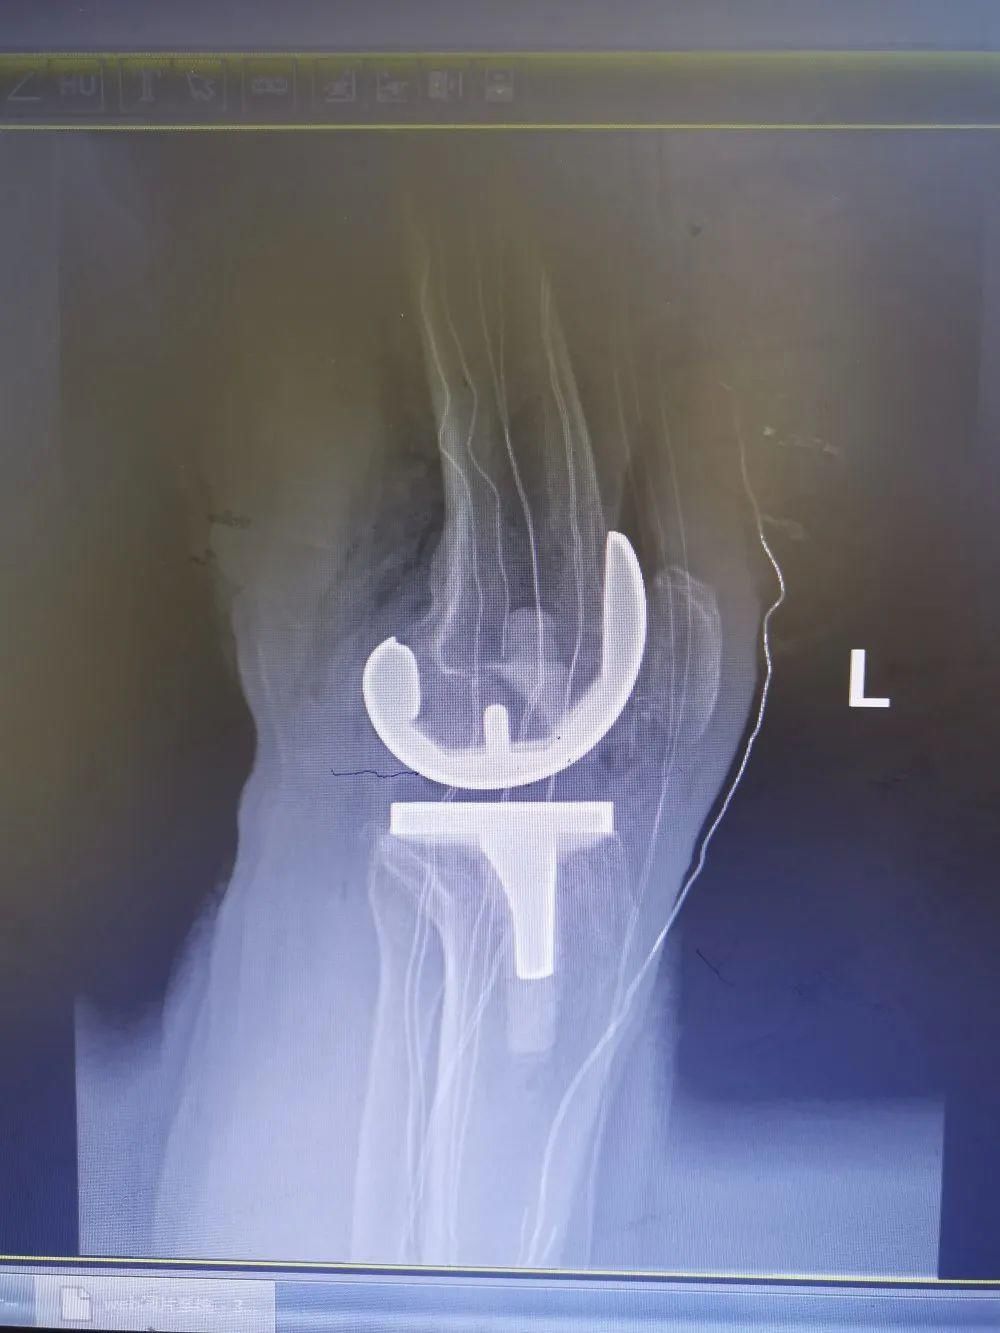

在贵州华夏骨科医院经过医生详细地问诊、拍片,确定彭爷爷患的是双膝关节退行性骨关节炎,要置换双膝关节,才能解决疼痛。